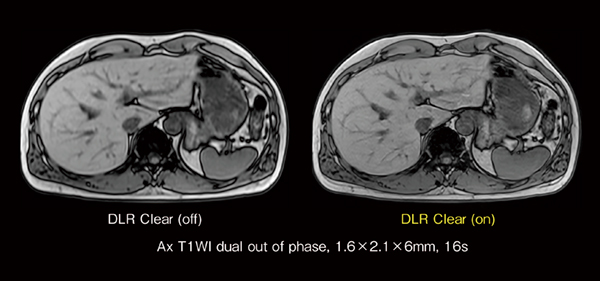

AI技術を活用した画質向上技術

今回,新たに搭載した「DLR Clear」は,AI技術を活用した画質向上技術であり,MRIの撮像原理上発生するトランケーションアーチファクトの低減や画像先鋭度を向上することが期待できます。図6に頸椎のT2強調画像の矢状断を示していますが,DLR Clearを付加することにより,しま状のトランケーションアーチファクトが低減していることがわかります。また,図7に肝臓のT1強調画像を示していますが,同じピクセルサイズで撮像しているにもかかわらず,DLR Clearの画像先鋭度が向上していることがわかります。このDLR Clearは,FSEやDWIなどの2Dシーケンスのみならず,RADAR(RADial Acquisition Regime)のようなradial scanや3Dシーケンスにも幅広く適応することが可能であり,MRIの画質向上が期待できる機能です。

図7 DLR Clearによる画像先鋭度の向上

左右の画像とも同じピクセルサイズで撮像した腹部T1強調画像。DLR Clearを使用すると同じピクセルサイズで撮像しているにもかかわらず,画像先鋭度が向上していることがわかる。